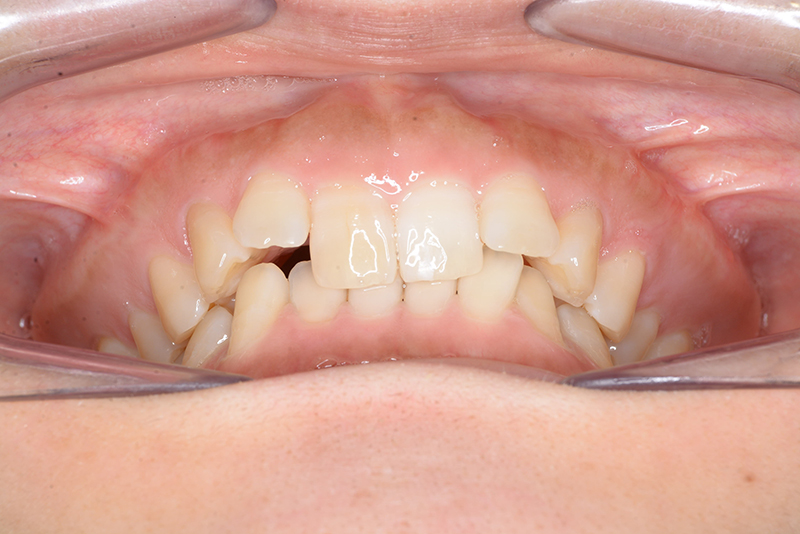

主訴 噛み合わせが深い 診断名 アングルⅡ級2類症例

初診時年齢 33歳1ヵ月 性別 動的治療期間 15ヵ月

口腔内所見 大臼歯、犬歯関係はⅡ級で、上顎中切歯は舌側傾斜しており、over jet1.5mm,over bite 6.0mmいわゆるⅡ級2類であった。